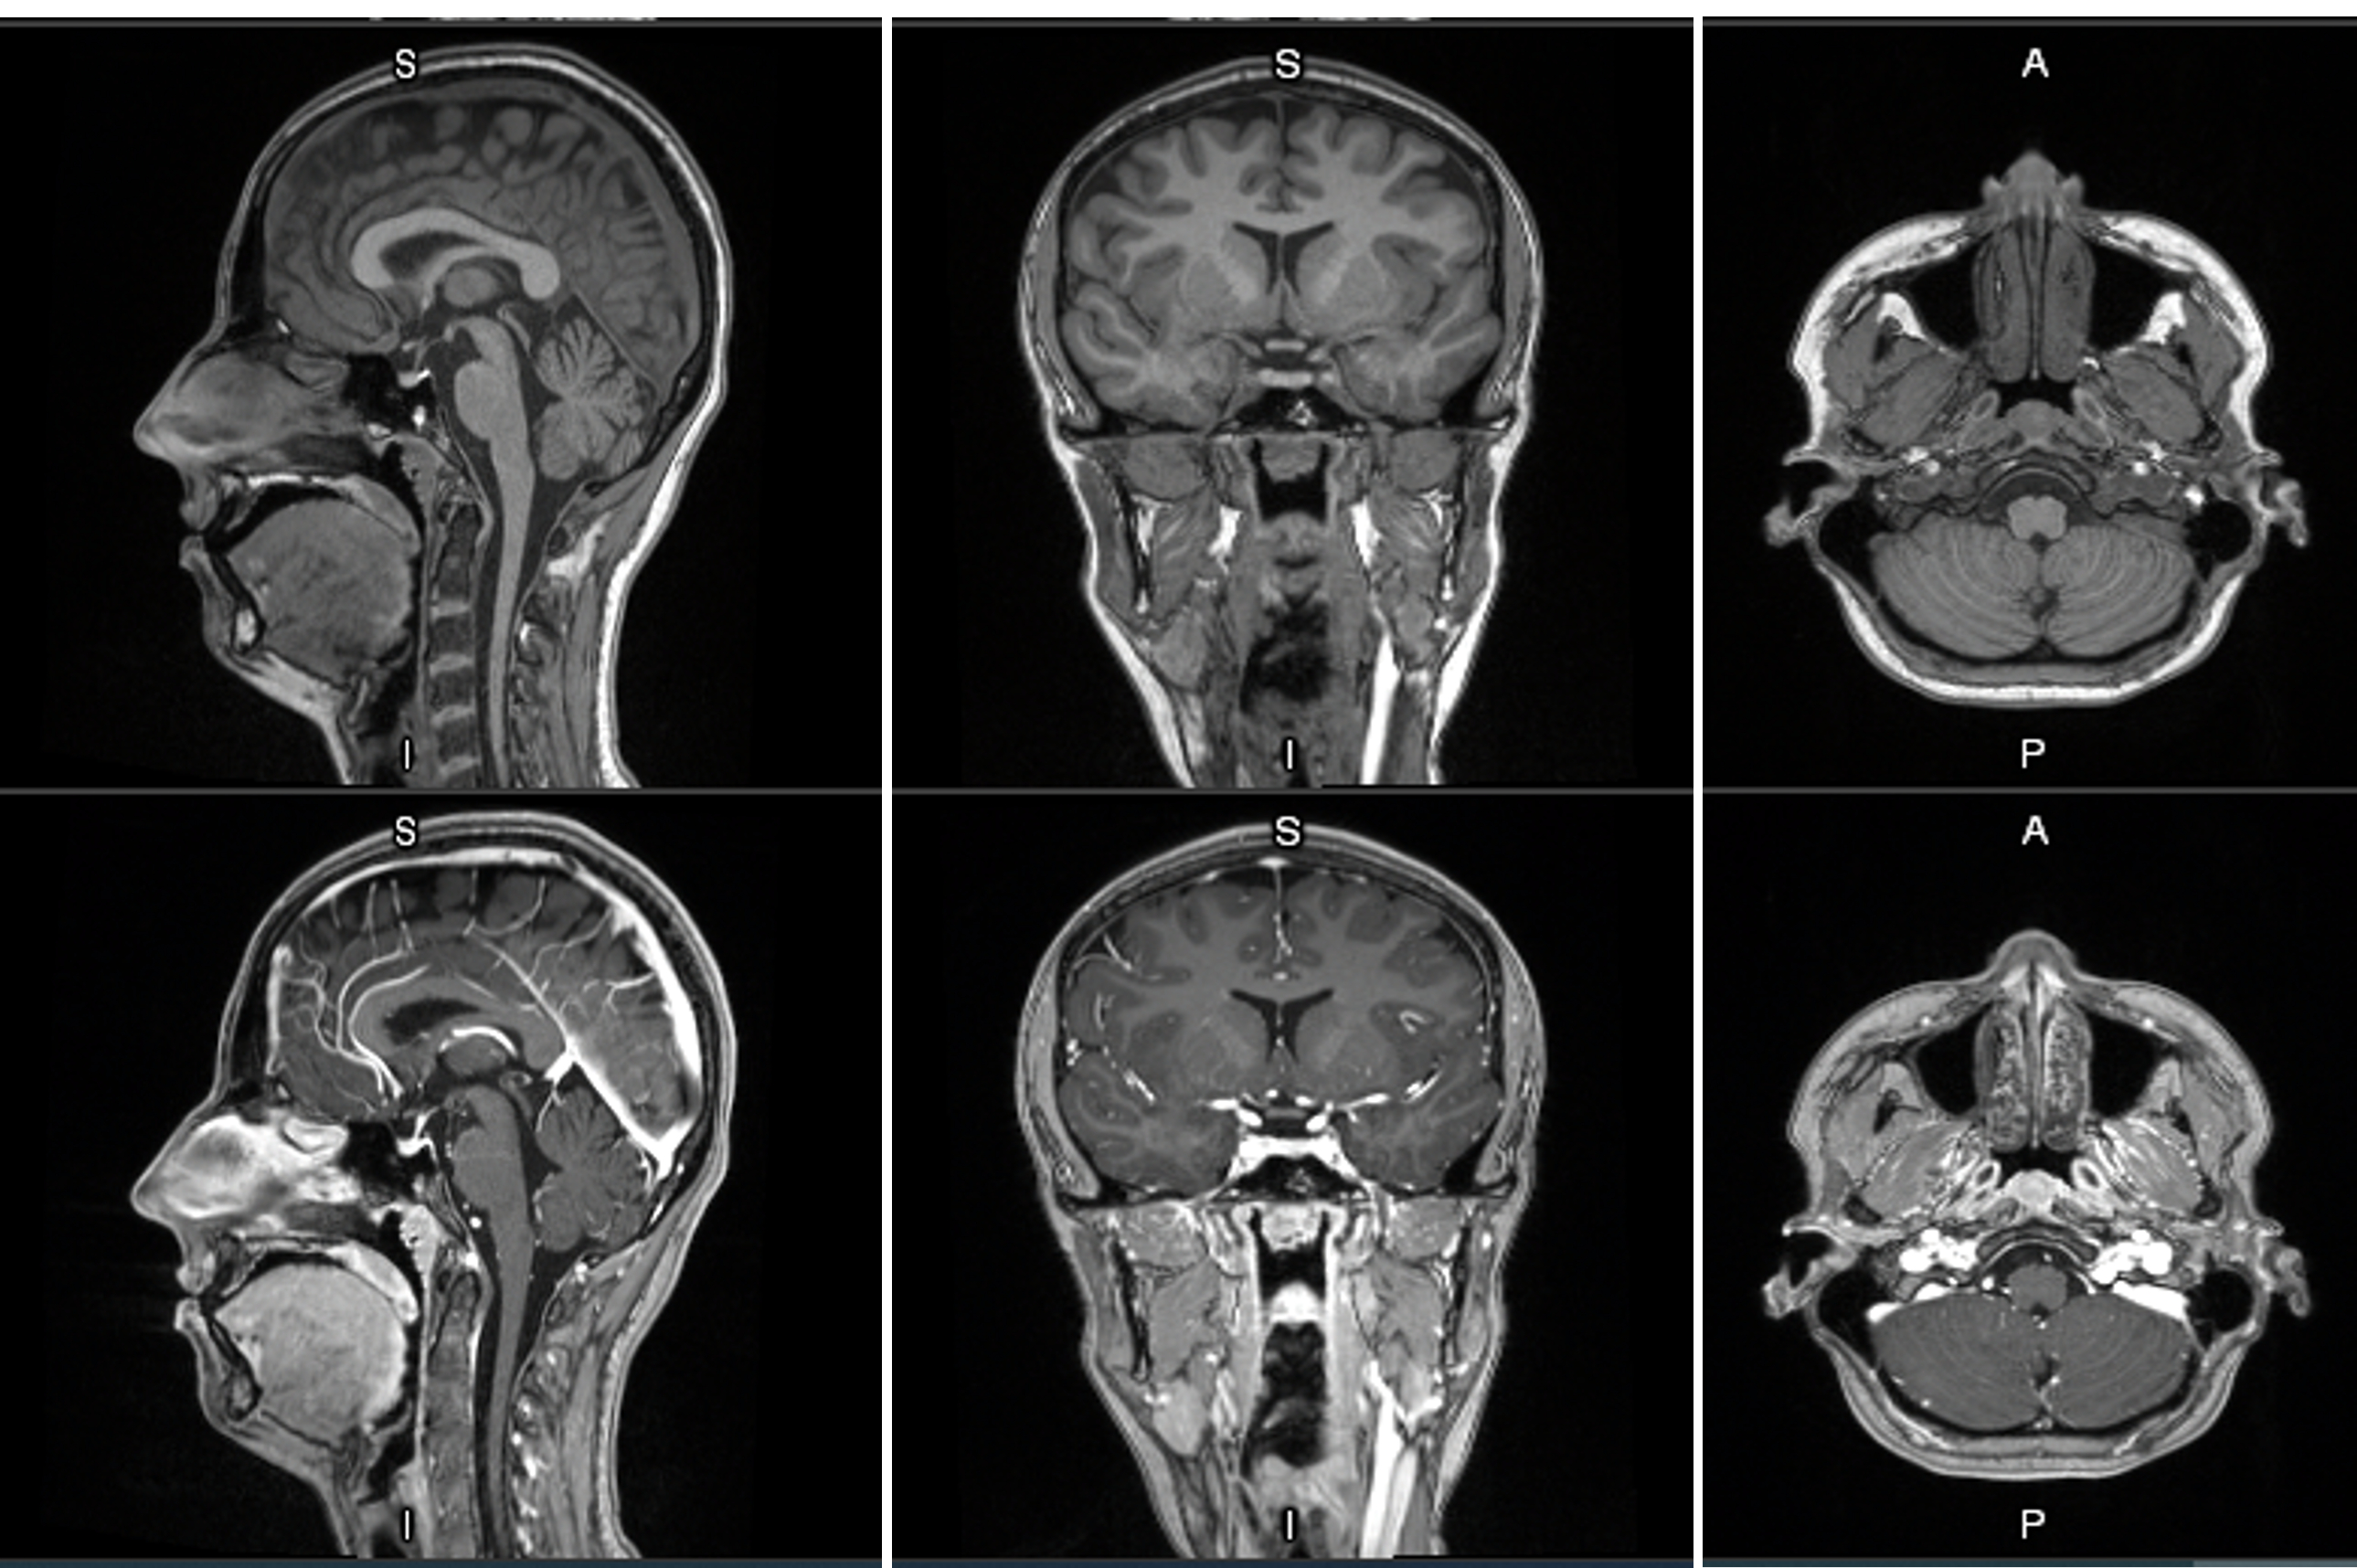

MRI contrast agents enhance the visualization of abnormal structures or lesions during imaging procedures and help clinicians better distinguish between healthy and diseased tissue. Mangaciclanol is intended for general-purpose MR imaging and demonstrates comparable relaxivity (the ability to enhance signal intensity) to market-leading gadolinium-based agent, gadobutrol, with early clinical images suggesting similar diagnostic capability. Unlike gadolinium, which is a rare-earth metal, manganese is present in our food, and is an endogenous element, naturally occurring and autoregulated in the body. The macrocyclic ‘cage-like’ structure of mangaciclanol lessens the possibility of retention.